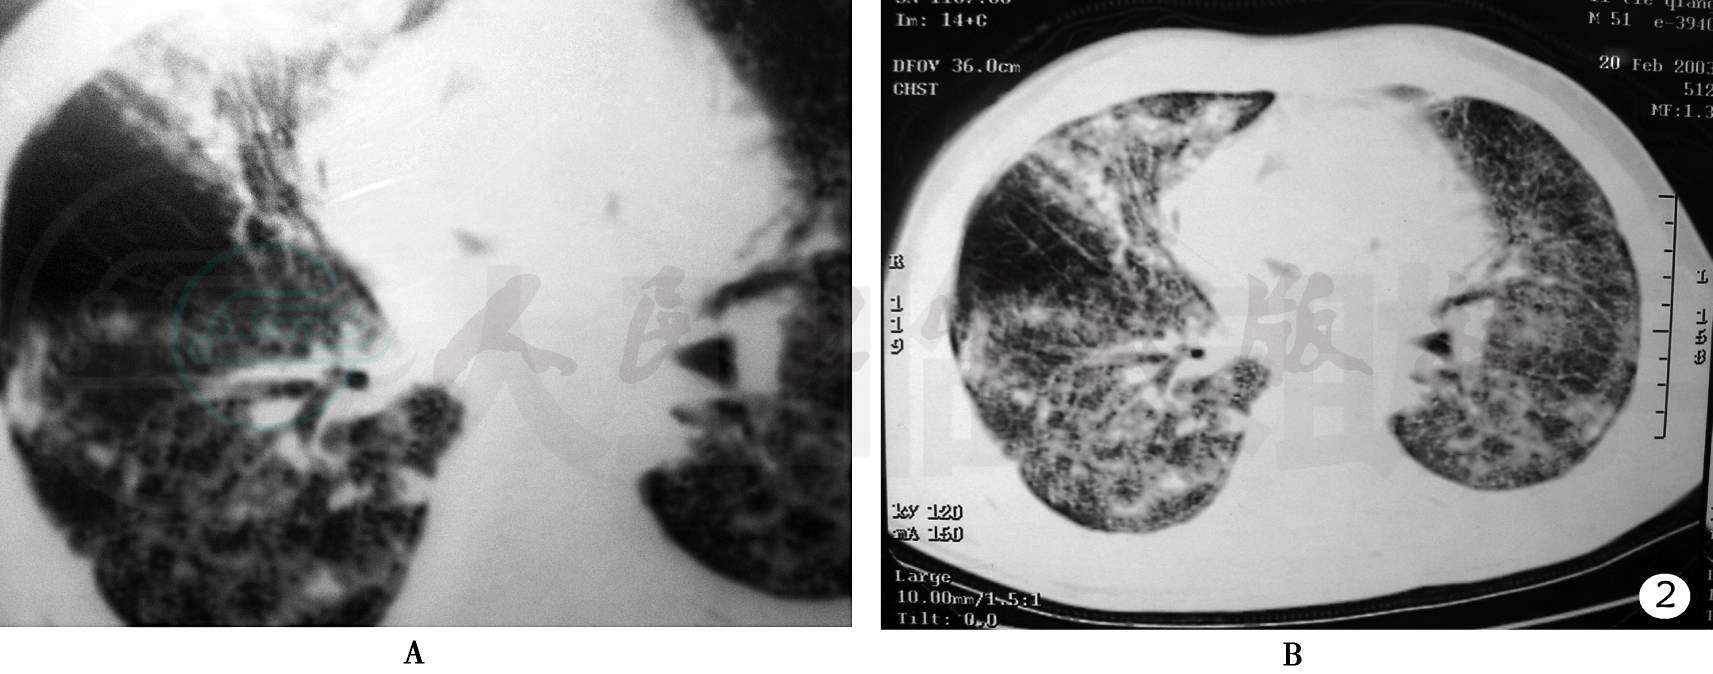

肺部CT检查

双肺野呈弥漫性磨玻璃样密度增高影,以两中下肺明显,尤以左下肺明显,肺尖部病变较少,双侧胸膜增厚,纵隔淋巴结不肿大(图2)。

图2 肺CT(2003)